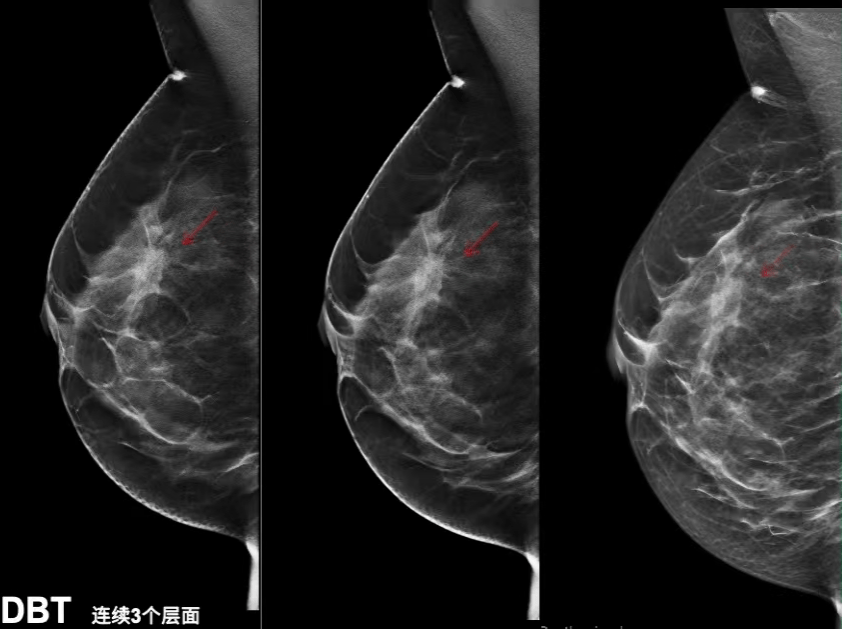

近年来,随着医学影像技术的快速发展,超声、CT、MRI等影像手段已经成为临床疾病诊断的重要依据。其中,乳腺超声由于具有无创、无辐射、成本较低等优势,被广泛应用于乳腺疾病的早期筛查与辅助诊断。然而,乳腺超声图像通常具有噪声多、对比度低、边界模糊等特点,对医生的阅片经验和专业能力依赖较高,在实际诊断过程中容易受到主观因素影响。因此,如何利用计算机技术对乳腺超声图像进行自动分析与识别,成为近年来医学影像智能化研究的重要方向。

随着深度学习技术的发展,基于卷积神经网络(CNN)的医学图像分类方法在乳腺肿瘤检测、病灶识别等任务中取得了较好的效果。但传统CNN模型主要依赖局部卷积操作提取特征,在处理复杂结构关系或全局信息时仍存在一定局限。近年来,Transformer结构在计算机视觉领域逐渐兴起,其中Vision Transformer(ViT)通过自注意力机制能够更好地建模图像的全局特征关系,在多种视觉任务中表现出较强的特征表达能力。同时,图神经网络(Graph Neural Network,GNN)在处理结构化数据和关系信息方面具有独特优势,可以通过构建节点之间的连接关系来捕捉更丰富的结构特征。

在此背景下,将Vision Transformer与图神经网络相结合,为医学影像分析提供了一种新的建模思路。通过先利用ViT对图像进行特征提取,再借助GNN刻画图像patch之间的潜在结构关系,有望进一步提升模型对复杂医学影像特征的表达能力。基于这一思路,本文以公开的乳腺超声图像数据集为研究对象,构建了一个融合ViT与GNN的乳腺超声图像分类模型,对正常、良性和恶性三类乳腺组织进行自动识别,并通过实验评估模型在乳腺疾病辅助诊断中的应用效果。